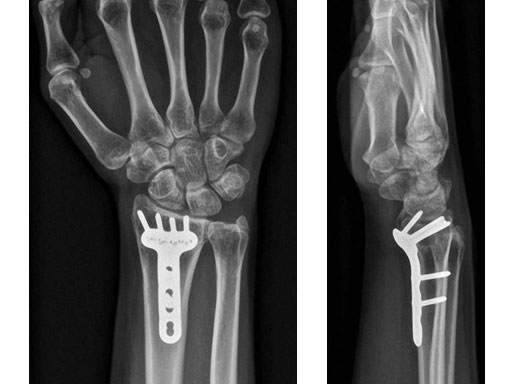

Case 4: Open radius shaft fracture

A 59-year-old farmer suffered a crush injury with an open forearm fracture (AO22 C2, Gustilo and Anderson IIIB) (Fig 1). Initial stabilization was carried out by external fixator (Fig 2). After four rounds of debridement and capillary ingrowth of a splitting skin graft at day 17, the VA LCP Extra Long Two-Column plate was used for fixation of the radius. A 2.7 mm LCP Condylar Plate was used for fixation of the ulna. The plates provided good stability for a functional after-treatment.

At the 3-month follow-up, the patient was full weight bearing with healing fractures (Fig 3).